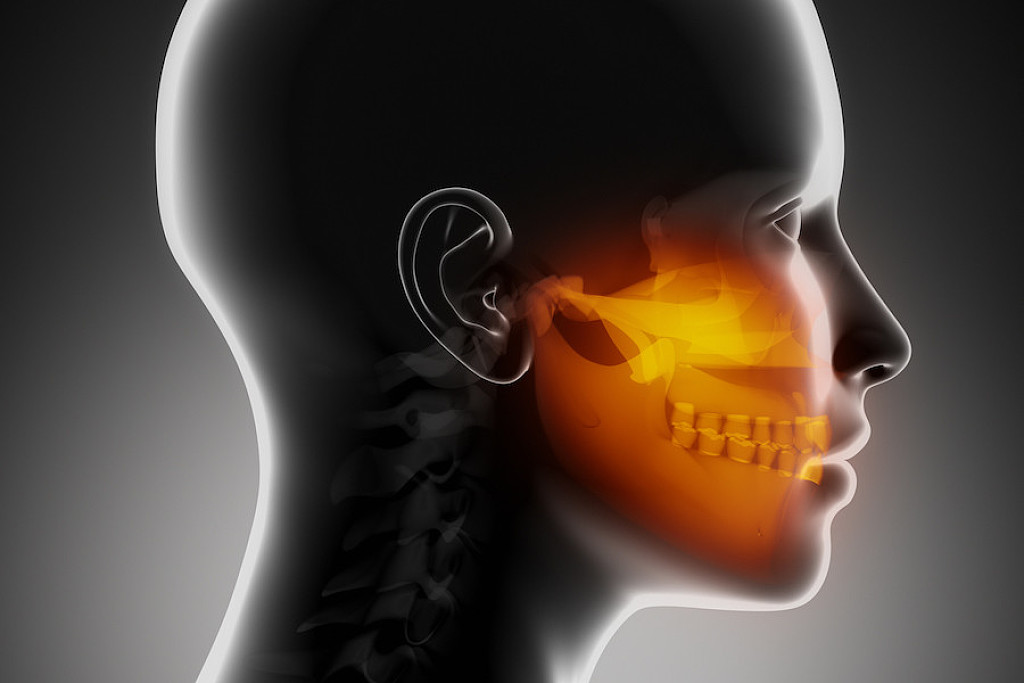

Four Symptoms of Jaw Cancer

Learning about oral cancer can be frightening—but education leads to early detection, and early detection is key to a better diagnosis. Because oral cancer can develop anywhere inside your mouth, it can manifest in your jaw as well. Here, we’ll look at four jaw cancer symptoms (as well as symptoms that aren’t jaw cancer, such as TMJ disorders) to watch out for and what you can do to address them as early as possible.

Compared to other cancers, oral cancer is less common—according to the American Cancer Society, about 54,000 will be diagnosed with oral cancer in 2021. Oral cancer also affects men twice as often as women, and the average age of diagnosis is 62. But let’s focus specifically on cancer of the jaw. According to the Merck Manual, jaw cancer can occur either on the upper jaw, known as the maxilla, or the lower jaw, known as the mandible. If you experience any of the following jaw cancer symptoms, be sure to seek an evaluation by your dental professional.

Swelling of the Jaw

A primary symptom of cancer in the jaw is swelling in the face, palate, or area of your jaw that supports your teeth. This swelling may be visible on the side of your face, but it can also occur inside your mouth. You may notice swelling in the roof of your mouth or beneath your teeth, depending on the location of the tumor. The growth of a tumor inside the bone may be the cause of this inflammation—and should be brought up with a dental professional as soon as possible.

Jaw Pain

Jaw pain caused by a tumor is one symptom of cancer in the jaw. According to The Mayo Clinic, while jaw tumors are rare and usually benign, they can also be aggressive and spread to other parts of the mouth’s bone and tissue, and cause teeth to be displaced, which can be painful. If your jaw is in pain and you’re not sure why, be careful not to dismiss it as a toothache—reach out to your dental professional for a proper diagnosis. Keep in mind this pain could also be due to TMJ disorder as opposed to cancer symptoms. However, if your dental professional does see a tumor or thinks one might be present, they’ll order imagining scans to examine your jaw further. If they find a tumor, they’ll likely order a biopsy to study the tumor and determine the best treatment plan.